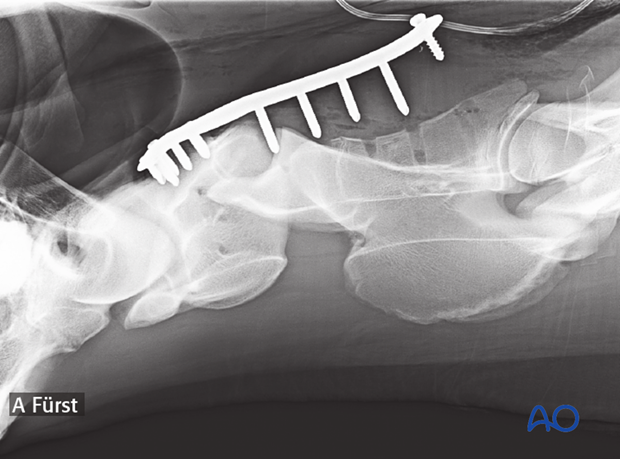

The subluxation was treated using a human distal femur plate to perform an arthrodesis in C1-C2. The screws didn't engage enough bone and the fixation became unstable after recovery.

Alternatively, a human distal femur plate can be used to improve the arthrodesis of C1-C2.

Minimal plate bending is needed.

With the reduction forceps in position, the appropriately sized plate is applied to the ventral aspect of C1 and C2.

One cortex screw is inserted into each vertebra in load fashion. The correct length of the screws is determined with the help of fluoroscopy.